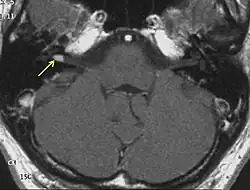

![]() МРТ головного мозга. Невринома слухового нерва указана стрелками | |

На МРТ выявляется ровный контур опухоли и по её периферии полоска сигнала так называемой «ликворной щели», деформация мозжечка и ствола головного мозга. При распространении невриномы во внутренний слуховой проход внекананальная её часть имеет вид «свисающей капли»[30].

Приблизительно 2/3 неврином выглядят гипоинтенсивными, а одна треть изоинтенсивными на Т1-взвешенных томограммах. На Т2-взвешенных томограммах невриномы характеризуются повышением сигнала, степень которого варьирует. Участки гетерогенно изменённого сигнала (вследствие образования кист) характерны для новообразований больших размеров (как правило, более 3 см). Все невриномы интенсивно накапливают контрастные вещества, более чем в 70 % случаев их накопление гетерогенно[30].